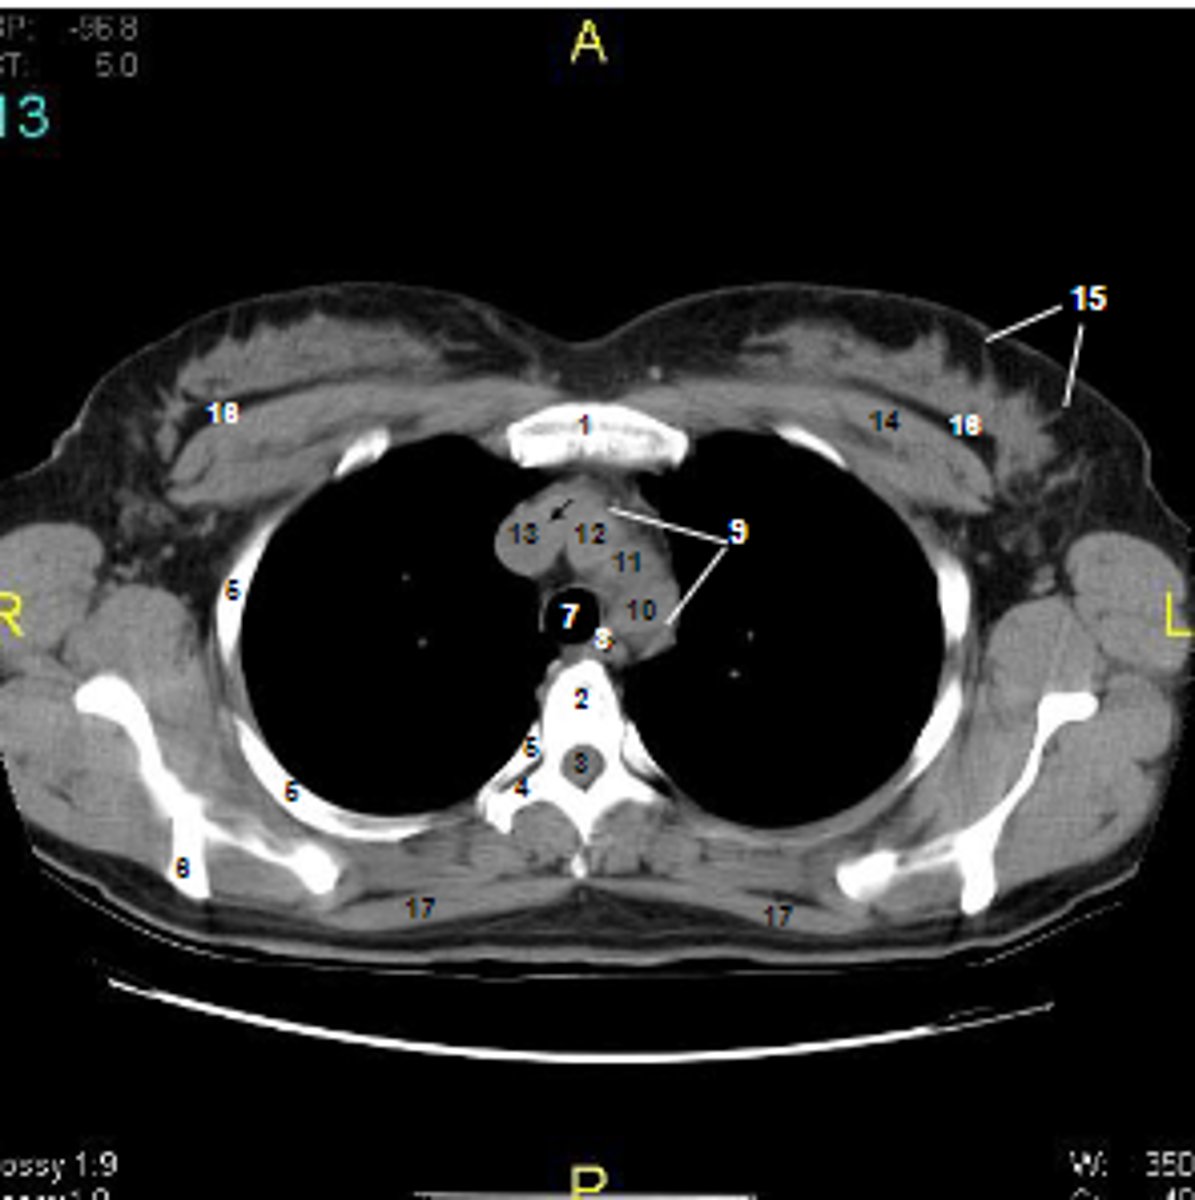

1

at what number is the sternum

2

at what number is the vertebral body

3

at what number is the vertebral canal/ spinal cord

4

at what number is the transverse process of vertebra

5

at what number is the rib

6

at what number is the spine of scapula

7

at what number is the trachea

8

at what number is the esophagus

9

at what number is the arch of aorta

10

at what number is the left subclavian artery

11

at what number is the common carotid artery

12

at what number is the brachiocephalic trunk

13

at what number is the superior vena cava

14

at what number is pectoralis major

15

at what number are Cooper's ligaments

16

at what number is the retromammary space

17

at what number is trapezius